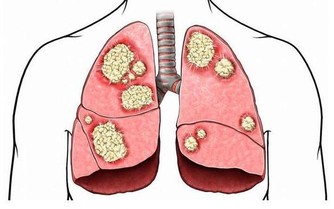

這種放屁可能是癌症的徵兆:

消化專家進一步提醒,當屁噴糞便或粘液時,有可能是直腸有炎症或腫瘤,不容忽視。